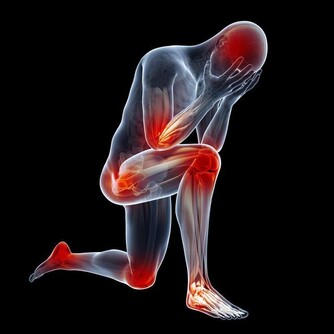

3、跌打淤腫的人

大家知道,花生具有止血的作用,是因為含有一種促凝血因子,可以縮短凝血時間,而如果是跌打淤腫的人,吃太多花生的話,可能會導致淤血不散,跌打腫痛的情況可能會加重的。